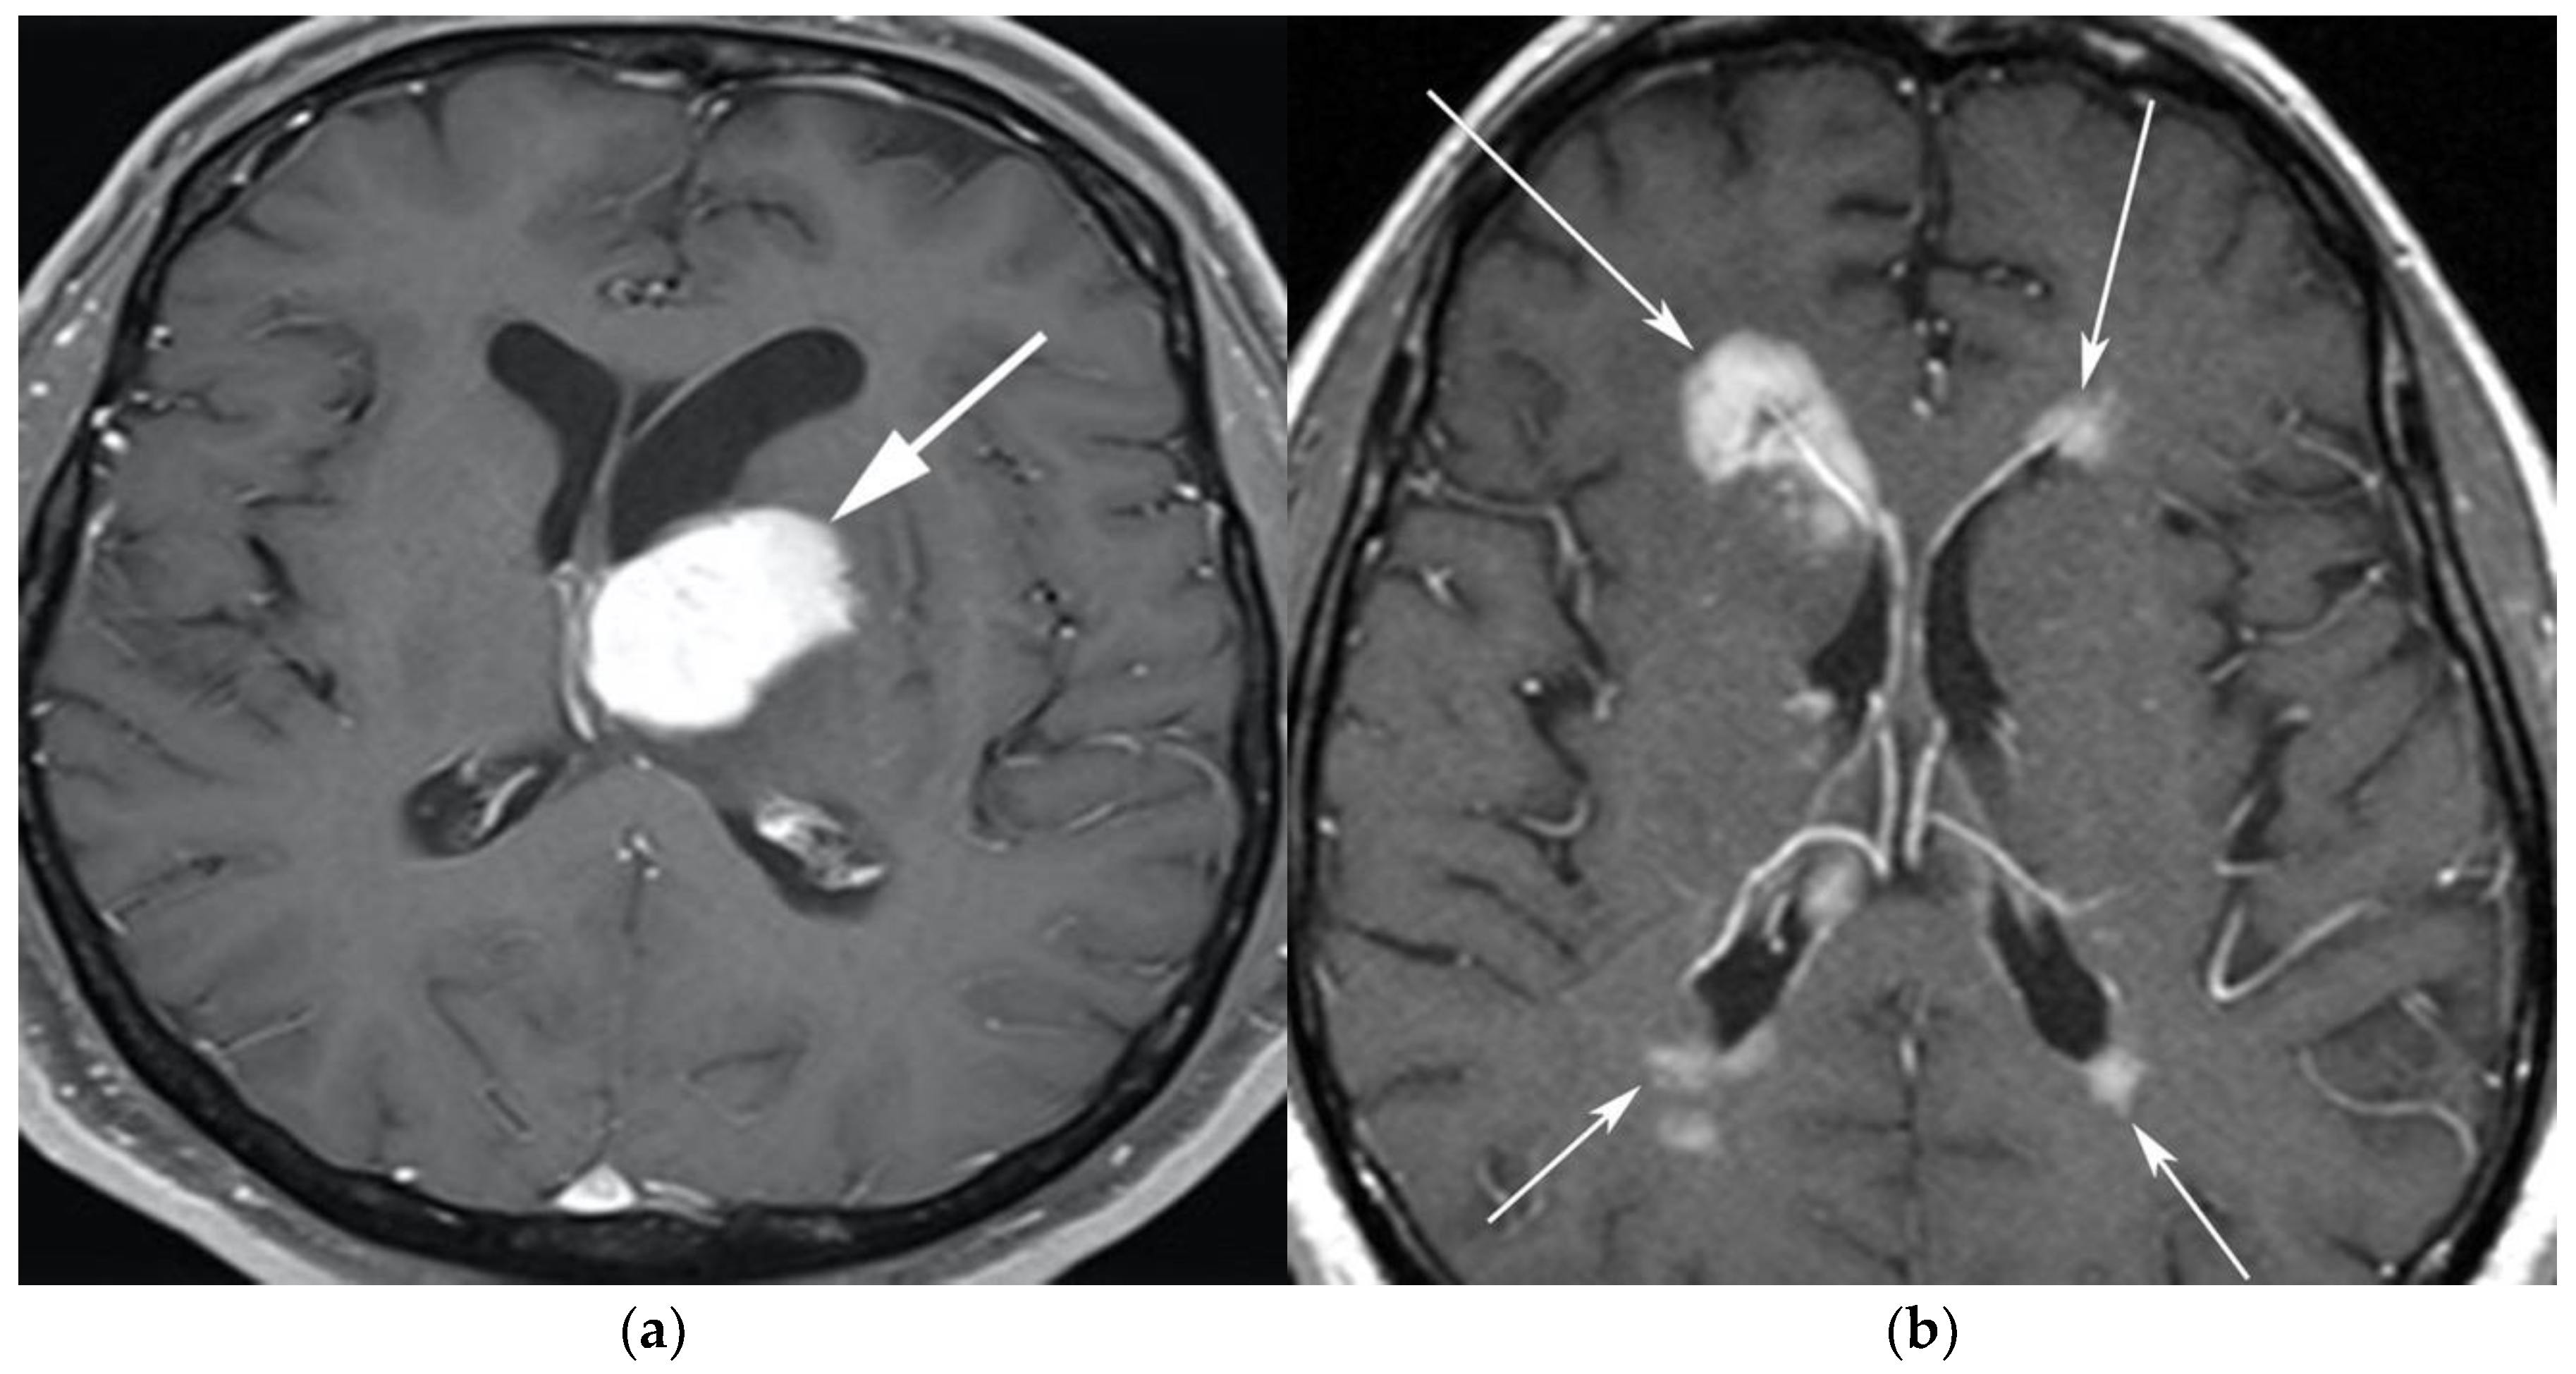

The classic imaging appearance of PCNSL is a focal solitary mass or multiple masses within the brain parenchyma. On CT, PCNSL often shows homogenously hyperdense lesions due to high tumor cellularity with homogenous enhancement and a predilection for the deep gray matter and deep nuclei, periventricular trigon, and corpus callosum that often abuts the sub ependymal/ventricular or meningeal surfaces [9]. Involvement of the meninges is most commonly seen in secondary lymphoma but can also be seen in PCNSL [13]. On MRI, PCNSL tumors tend to be hypointense to isointense on T1-weighted sequences (T1W) and isointense to hyperintense on T2-weighted sequences (T2W) with intense enhancement on post-contrast images (Figure 1).

Figure 1.

A 65-year-old man presenting with headache. (a) Axial T1 post-contrast fat-suppressed image shows homogenous enhancing mass within the left thalamus (white arrow) with mass effect on the 3rd ventricle and left putamen laterally. (b) Axial T1 post-contrast fat-suppressed images in a different patient show infiltrative periventricular soft tissue masses (white arrows). Both cases were pathologically proven primary central nervous system lymphoma-diffuse large B-cell histologic subtype.

Special sequences such as apparent diffusion coefficient (ADC) maps help differentiate PCNSL from high-grade tumors such as glioblastoma multiforme (GBM). PCNSL demonstrates marked diffusion restriction on diffusion-weighted images (DWI) with lower ADC values compared to GBM due to tumor restriction in lymphoma cells. The main role of 18F-FDG PET/CT in CNS lymphoma is to differentiate PCNSL vs. disseminated systemic lymphoma involving the CNS [14]. Additionally, 18F-FDG PET/CT can help in distinguishing PCNSL from mimicking disorders such as hypometabolic intracranial opportunistic infections including CNS toxoplasmosis [15,16,17,18]. Imaging findings of LC include diffuse, non-mass-like lesions within both hemispheres involving the white matter, corticospinal tracts (CST), and deep gray matter. These lesions show patchy contrast enhancement and diffuse abnormal T2W hyperintensity. Unlike PCNSL, LC shows variable restriction on DWI [19]. Regions commonly affected in LC include the subcortical, deep, and periventricular white matter, CST, U-fibers, corpus callosum, and gray matter, with less frequent involvement of the spinal cord compared to PCNSL [12]. Contiguous spread of lesions from the cerebral white matter to the brain stem along the corticospinal tract (CST) is a notable feature of LC, which can involve both the brain and brain stem (Figure 2 and Figure 3). Unlike PCNSL, the characteristic neuroradiological findings of LC with 18F-FDG PET/CT have not yet been established; nevertheless, they are usually seen as hypermetabolic mass like lesions [8,20]. MRI spectroscopy (MRS) may help differentiate LC from other neurodegenerative or inflammatory conditions. On MRS, evidence of high cell membrane turnover (high choline peak), neuronal damage (decreased NAA levels), high lactate levels, and elevated lipids is typically demonstrated. Although many of these MRS features resemble high-grade gliomas and metastases, elevated lipids have been shown to be potentially useful to differentiate between these entities and LC [21]. The diagnosis of lymphomatosis cerebri should be considered in patients presenting with a rapidly progressive decline in cognitive function, dementia, or behavioral abnormalities. Imaging findings including diffuse bilateral hemispheric cortical spinal tract involvement and pathology may show predominant infiltration of the neuronal tracts without the formation of definite masses. It is crucial that diagnosis of LC is only made after the exclusion of other common etiologies as the clinical and imaging findings of LC can be misattributed to other diffuse infiltrative brain tumors, leukoencephalopathy, vasculopathy, degenerative disease, ischemic processes, infectious processes, and toxic demyelinating diseases in addition to dementias and other psychiatric disorders such as depression [8,12].